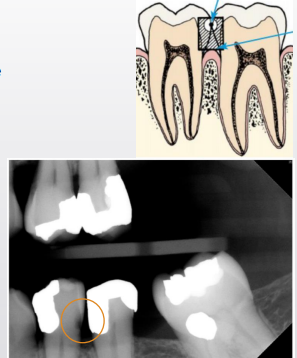

caries or cervical burn out

burnout

caries or cervical burnout

caries